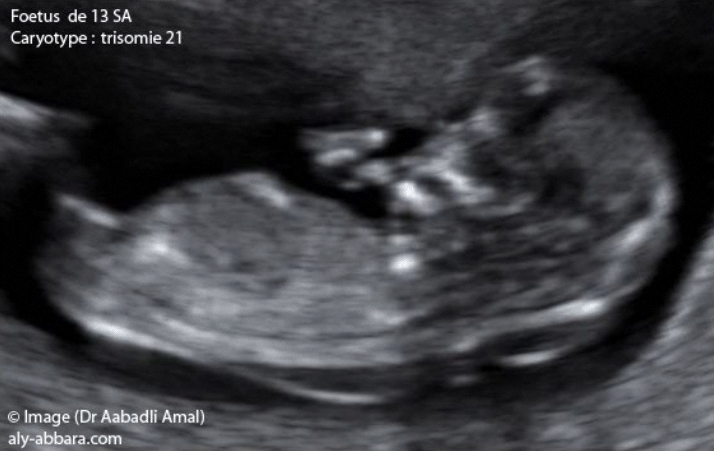

المثال الأول

سن الأم الحامل 31 سنة

سن الجنين 13 أسبوع (طول رأسي ذنبي = 66,8 مم)

شفافية قفوية = 3 مم

الصيغة الصبغية للجنين تكشف عن وجود تثلث الصبغي 21 |